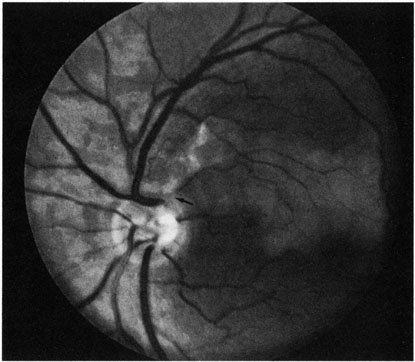

Hypoperfusion retinopathy is characterized by dot and blot hemorrhages in the midperiphery of the fundus, by venous tortuosity and engorgement, by microaneurysms, and by the occasional sludging of blood within the veins. Fluorescein angiography may show areas of capillary nonperfusion; it may also show microaneurysms in the midperiphery and slow arm to retina or arteriovenous transit time (Fig. 9A and 9B).174 The condition does not usually affect the posterior pole, and patients typically have normal visual acuity, although an occasional patient may have macular edema.174 The entire periphery of the eye is usually affected, although there may be more hemorrhages in one quadrant than another. Patients occasionally experience ocular discomfort or eye pain despite normal intraocular pressure. Reduction of the ophthalmic arterial pressure is a pathognomonic feature. Disc edema and disc collaterals are generally not present. The electroretinogram shows abnormalities in both the a- and b-waves (see Fig. 9C).

Fig. 9. Intravenous fluorescein angiogram of a patient with hypotensive or hypoperfusion retinopathy. A: There is a marked delay in the choroidal and retinal filling. B: In the recirculation of the angiogram, there is a characteristic staining of both arteries and veins. C: Electroretinogram shows normal a- and b-waves in the normal right eye (upper tracing) and marked redirection of the a- and b-waves in the affected left eye (lower tracing).